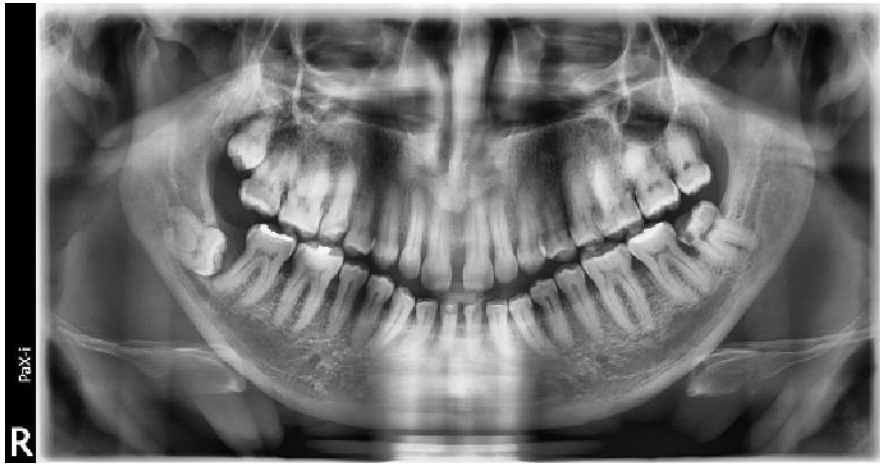

Figll Demonstrating in right side an integrated pattern of classification

(Distoangular impaction according to winter and class 3 position B according to Bell and Gregorys classification)

Impactions seen in fig. 11 are a good example of integrated pattern, reporting the type of impaction with this pattern give good estimation to the operator warn against complications like jaw bone fracture due to mass bone removal in all direction. This will help the operator to have preparedness for such mishaps and, warn the patient and get his consent for such an expected complication